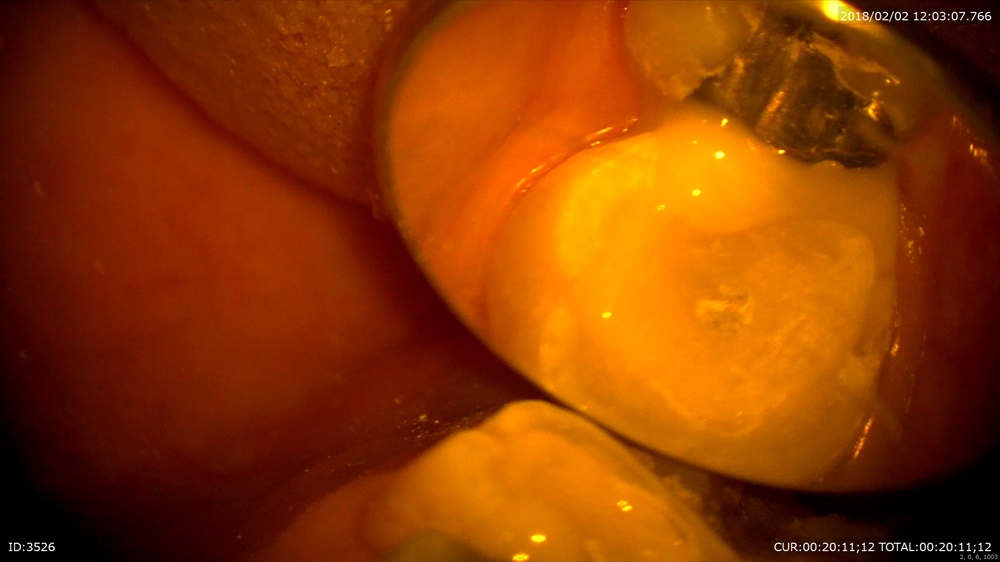

マイクロスコープで

次は精密根管治療の後の処置。MTAで根管充填し細菌感染を防ぐ為即日ファイバーコアを築造。

術前(精密根管治療)と本日